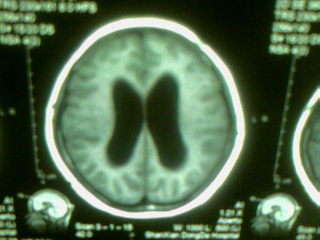

标题: MRI2125:女 45岁 头疼头晕3个月 [打印本页]

标题: MRI2125:女 45岁 头疼头晕3个月

1)考虑第四脑室脉络膜丛乳头状瘤,不排除室管膜瘤。2)阻塞性脑积水。

考虑 第四脑室室管膜瘤或脉络膜丛乳头状瘤伴梗阻性脑积水。

1)考虑第四脑室室管膜瘤,不排除脉络膜丛乳头状瘤。2)阻塞性脑积水。

考虑 第四脑室脑膜瘤或室管膜瘤或脉络膜丛乳头状瘤伴梗阻性脑积水